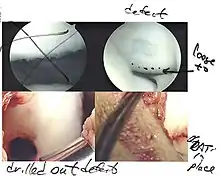

Intact lesions

If non-surgical measures are unsuccessful, drilling may be considered to stimulate healing of the subchondral bone. Arthroscopic drilling may be performed by using an antegrade (from the front) approach from the joint space through the articular cartilage, or by using a retrograde (from behind) approach through the bone outside of the joint to avoid penetration of the articular cartilage. This has proven successful with positive results at one-year follow-up with antegrade drilling in nine out of eleven teenagers with the juvenile form of OCD,[53] and in 18 of 20 skeletally immature people (follow-up of five years) who had failed prior conservative programs.[54]